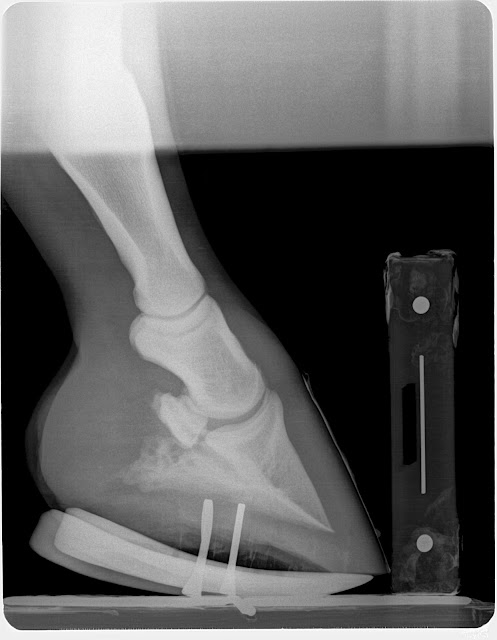

Club foot case: This horse lost the rocker rail shoe applie to the foot opposite the grade 3 club (which is also a club) and regular farrier applied a flat steel keg shoe to keep foot protected. Note the horn lamellar zone divergence. One could call this rotation which would be non specific. The divergence is created by the club syndrome stretching to lower horn to bone attachments. This is confirmed by evaluating the dermal-epidermal junction and measuring the horn zone compared to the lamellar zone. If the lamellar zone was larger than the horn zone one could conclude a laminitis as this is lamellar swelling. In this case it is chronic stretching of the lamellar bone secondary to the constant pull of the deep digital flexor unit.

The Grade 3 club grew more sole in the rocker rail than did the lower grade club in a flat shoe. This information tells us that placing the tendon sling in freedom with the rocker shoe allows better nutrient and blood circulation through unloading of the sole via reduced deep flexor tension. We placed the grade 2 club (Left Front) in a rockered trim with rockered steel keg shoe to also place the tendon sling in release. We will be to see a more rapid sole mass recovery in this hoof as well at the next reset. Owner reports excellent comfort and has adjusted very well to the new shoeing approach.

| 6 wks post rocker rail application additional 4mm of sole and cup starting to form. All this due to unloading of the deep flexor pull |